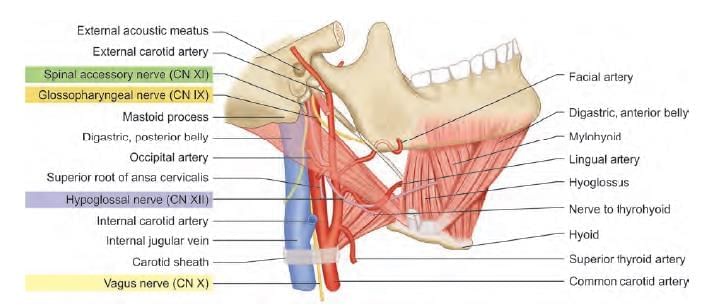

Patient undergoing surgery at the lateral part of skull. Postoperatively patient had aspirations without voice change. Nerve lesioned is: (AIIMS Nov 2019)

A patient with a fracture skull base at the temporo-occipital region, presented with difficulty in speaking post trauma. During investigation which structure should be tested which helps in diagnosis related with the points marked below? (INI-CET Nov 2021)